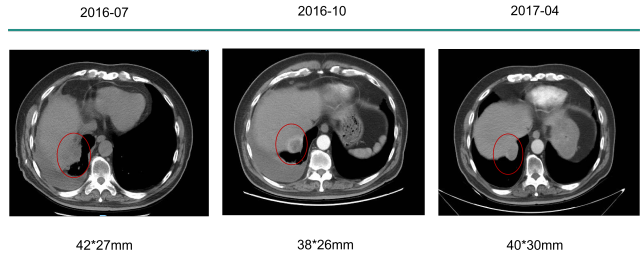

2016-07-2017-07

一线:多吉美

胸腔灌注:顺铂

影像学评估:SD -一线:多吉美

病情变化- 一线:多吉美